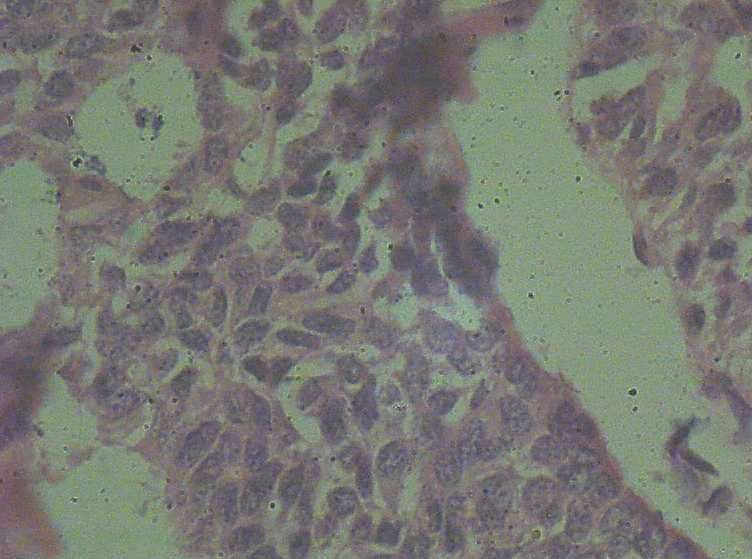

B3774乳腺积乳性包块?

女41岁,左腺包块。肉眼:不整形囊壁样组织,大小2*1.6*0.3CM,壁厚0.1—0.3,未触及结节,未见出血及坏死。

标签:乳腺纤维囊性增生症

报乳腺增生性腺病伴导管上皮不典型增生。

。图12-16可以看到导管上皮异形增生(导管上皮极向紊乱)